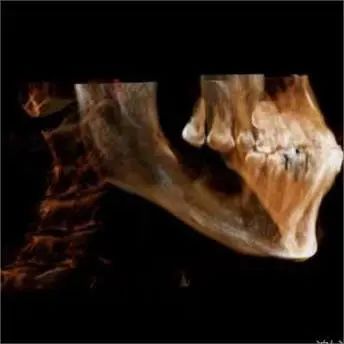

患者王先生(化名),58 岁。右下后牙缺失一年多,因对治疗过程和疼痛的恐惧,一直未做牙齿修复。

结果延误病情,导致对颌牙齿伸长,严重影响生活质量。

种植专家、口腔科杨彦春主任检查发现其口腔卫生环境较差,缺失的又是需要咀嚼的后牙,建议行种植修复手术。